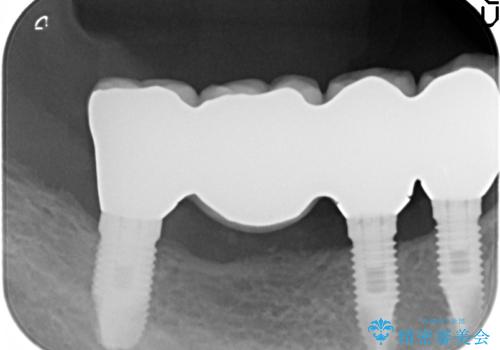

清掃性に優れたジルコニアカスタムアバットメント、ジルコニアクラウンを用いて機能性だけでなく審美性・予知性を高めます。

- 130万円(HAインプラント×3・骨造成・ジルコニアカスタムアバットメント×3・ジルコニアクラウン×4)費用は治療当時の料金となります